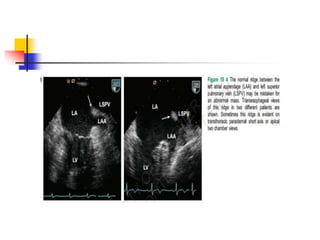

Coumadin Ridge

 A prominent muscle ridge is formed between the LAA

and the atrial insertion of the LUPV is referred to as

the coumadin ridge or "Q-tip" sign.

 This prominence is often misdiagnosed as thrombus .

 lack of mobility and characteristic location, best seen

in the ME two-chamber view, help distinguish it from

an abnormal structure.